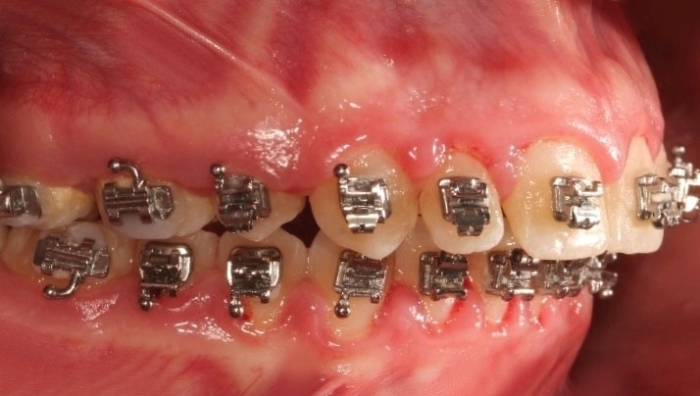

Mordida inicial